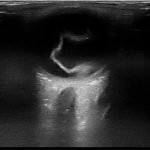

Bedside ocular ultrasound revealed a serpentine, hyperechoic membrane that appeared tethered to the optic disc posteriorly with hyperechoic material underneath. These findings are consistent with retinal detachment (RD) and associated retinal hemorrhage.

Findings on bedside ultrasound consistent with RD include a hyperechoic membrane floating in the posterior chamber. RD usuallyremain tethered to the optic disc posteriorly and do not cross midline, a feature distinguishing them from posterior vitreous detachments. Associated retinal hemorrhage, seen as hyperechoic material under the retinal flap, can often be seen.1,2 US can also distinguish between “mac-on” and “mac-off” detachments. If the retina is still attached to the macula (mac-on), central vision is preserved and emergent repair is essential before progression to a mac-off RD.2 In a prospective observational study, emergency physicians achieved 97% sensitivity, and 92% specificity in diagnosing this pathology on bedside US. Optic disc edema and vitreous hemorrhage accounted for the false positives.2 Emergent ophthalmology consultation was obtained for our patient who saw the patient the same day for vitrectomy.